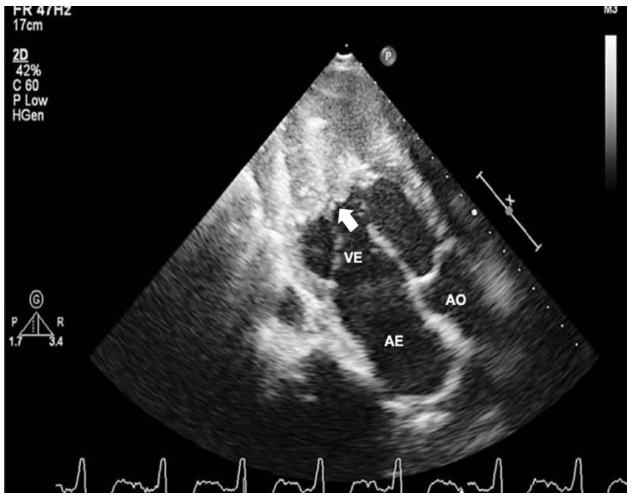

Analise a imagem a seguir.

(VE: ventrículo esquerdo; AE: átrio esquerdo; AO: aorta)

Entre as possíveis etiologias de miocardiopatias restritivas apresentadas a seguir, a mais associada ao padrão de obliteração apical fibrótica e/ou trombótica de um ou ambos os ventrículos, conforme visualizado no ecocardiograma acima(seta), é a

(VE: ventrículo esquerdo; AE: átrio esquerdo; AO: aorta)

Entre as possíveis etiologias de miocardiopatias restritivas apresentadas a seguir, a mais associada ao padrão de obliteração apical fibrótica e/ou trombótica de um ou ambos os ventrículos, conforme visualizado no ecocardiograma acima(seta), é a